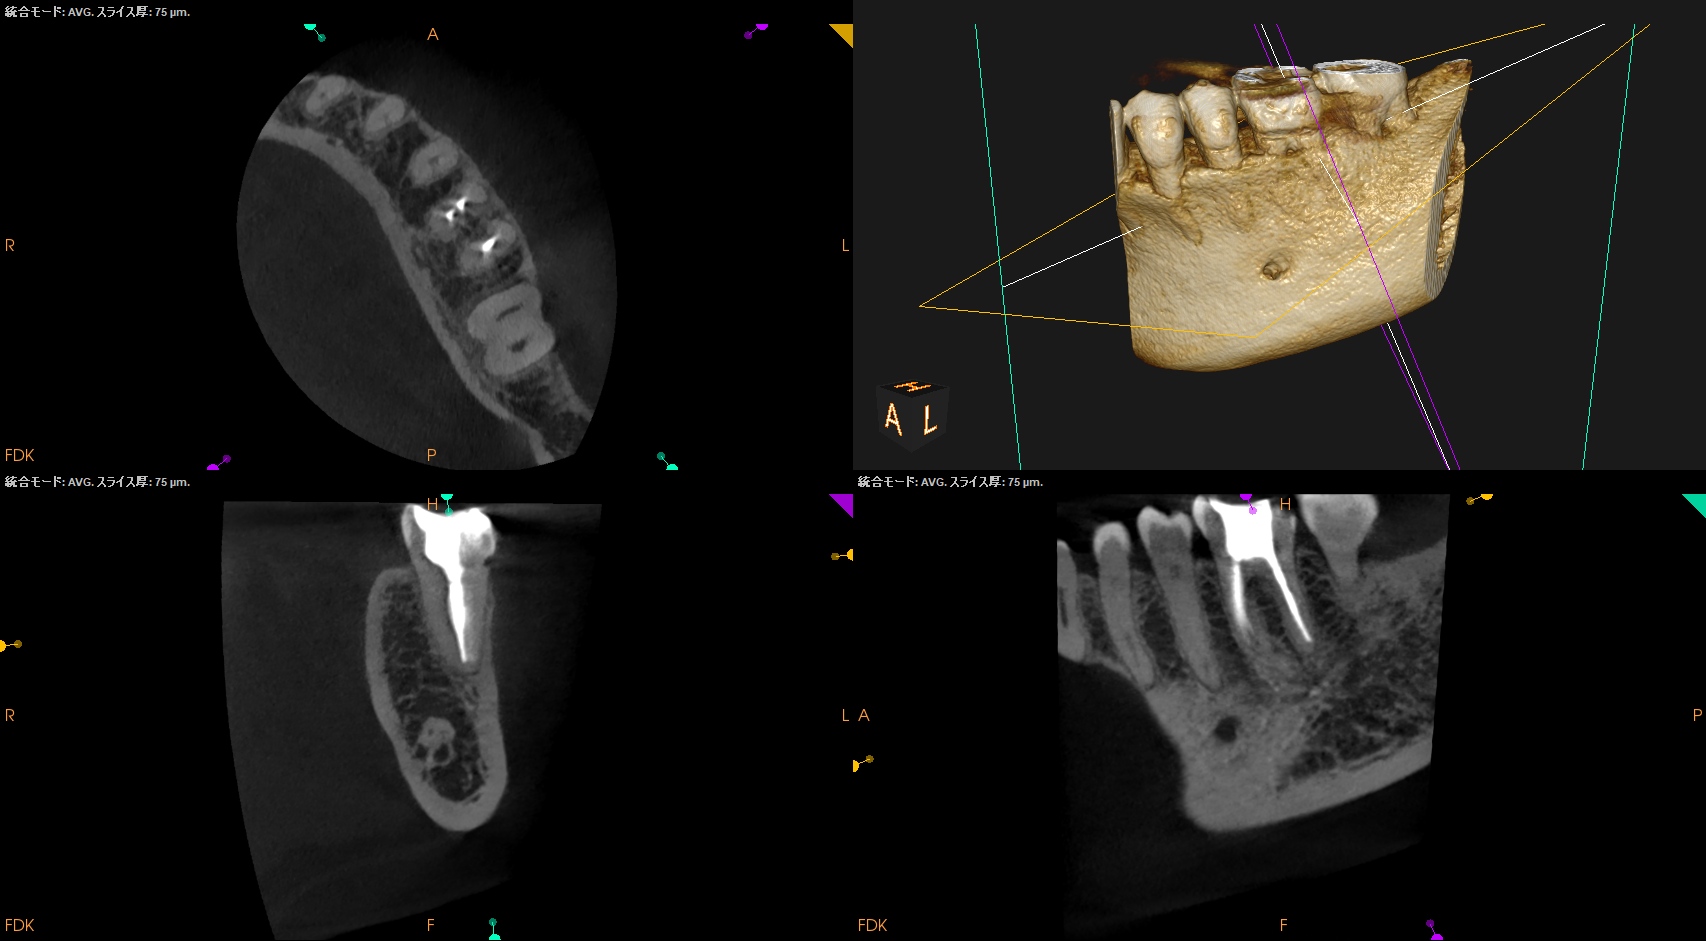

チャンバーオープンした。

やはり血まみれだ。

以下のように根管形成した。